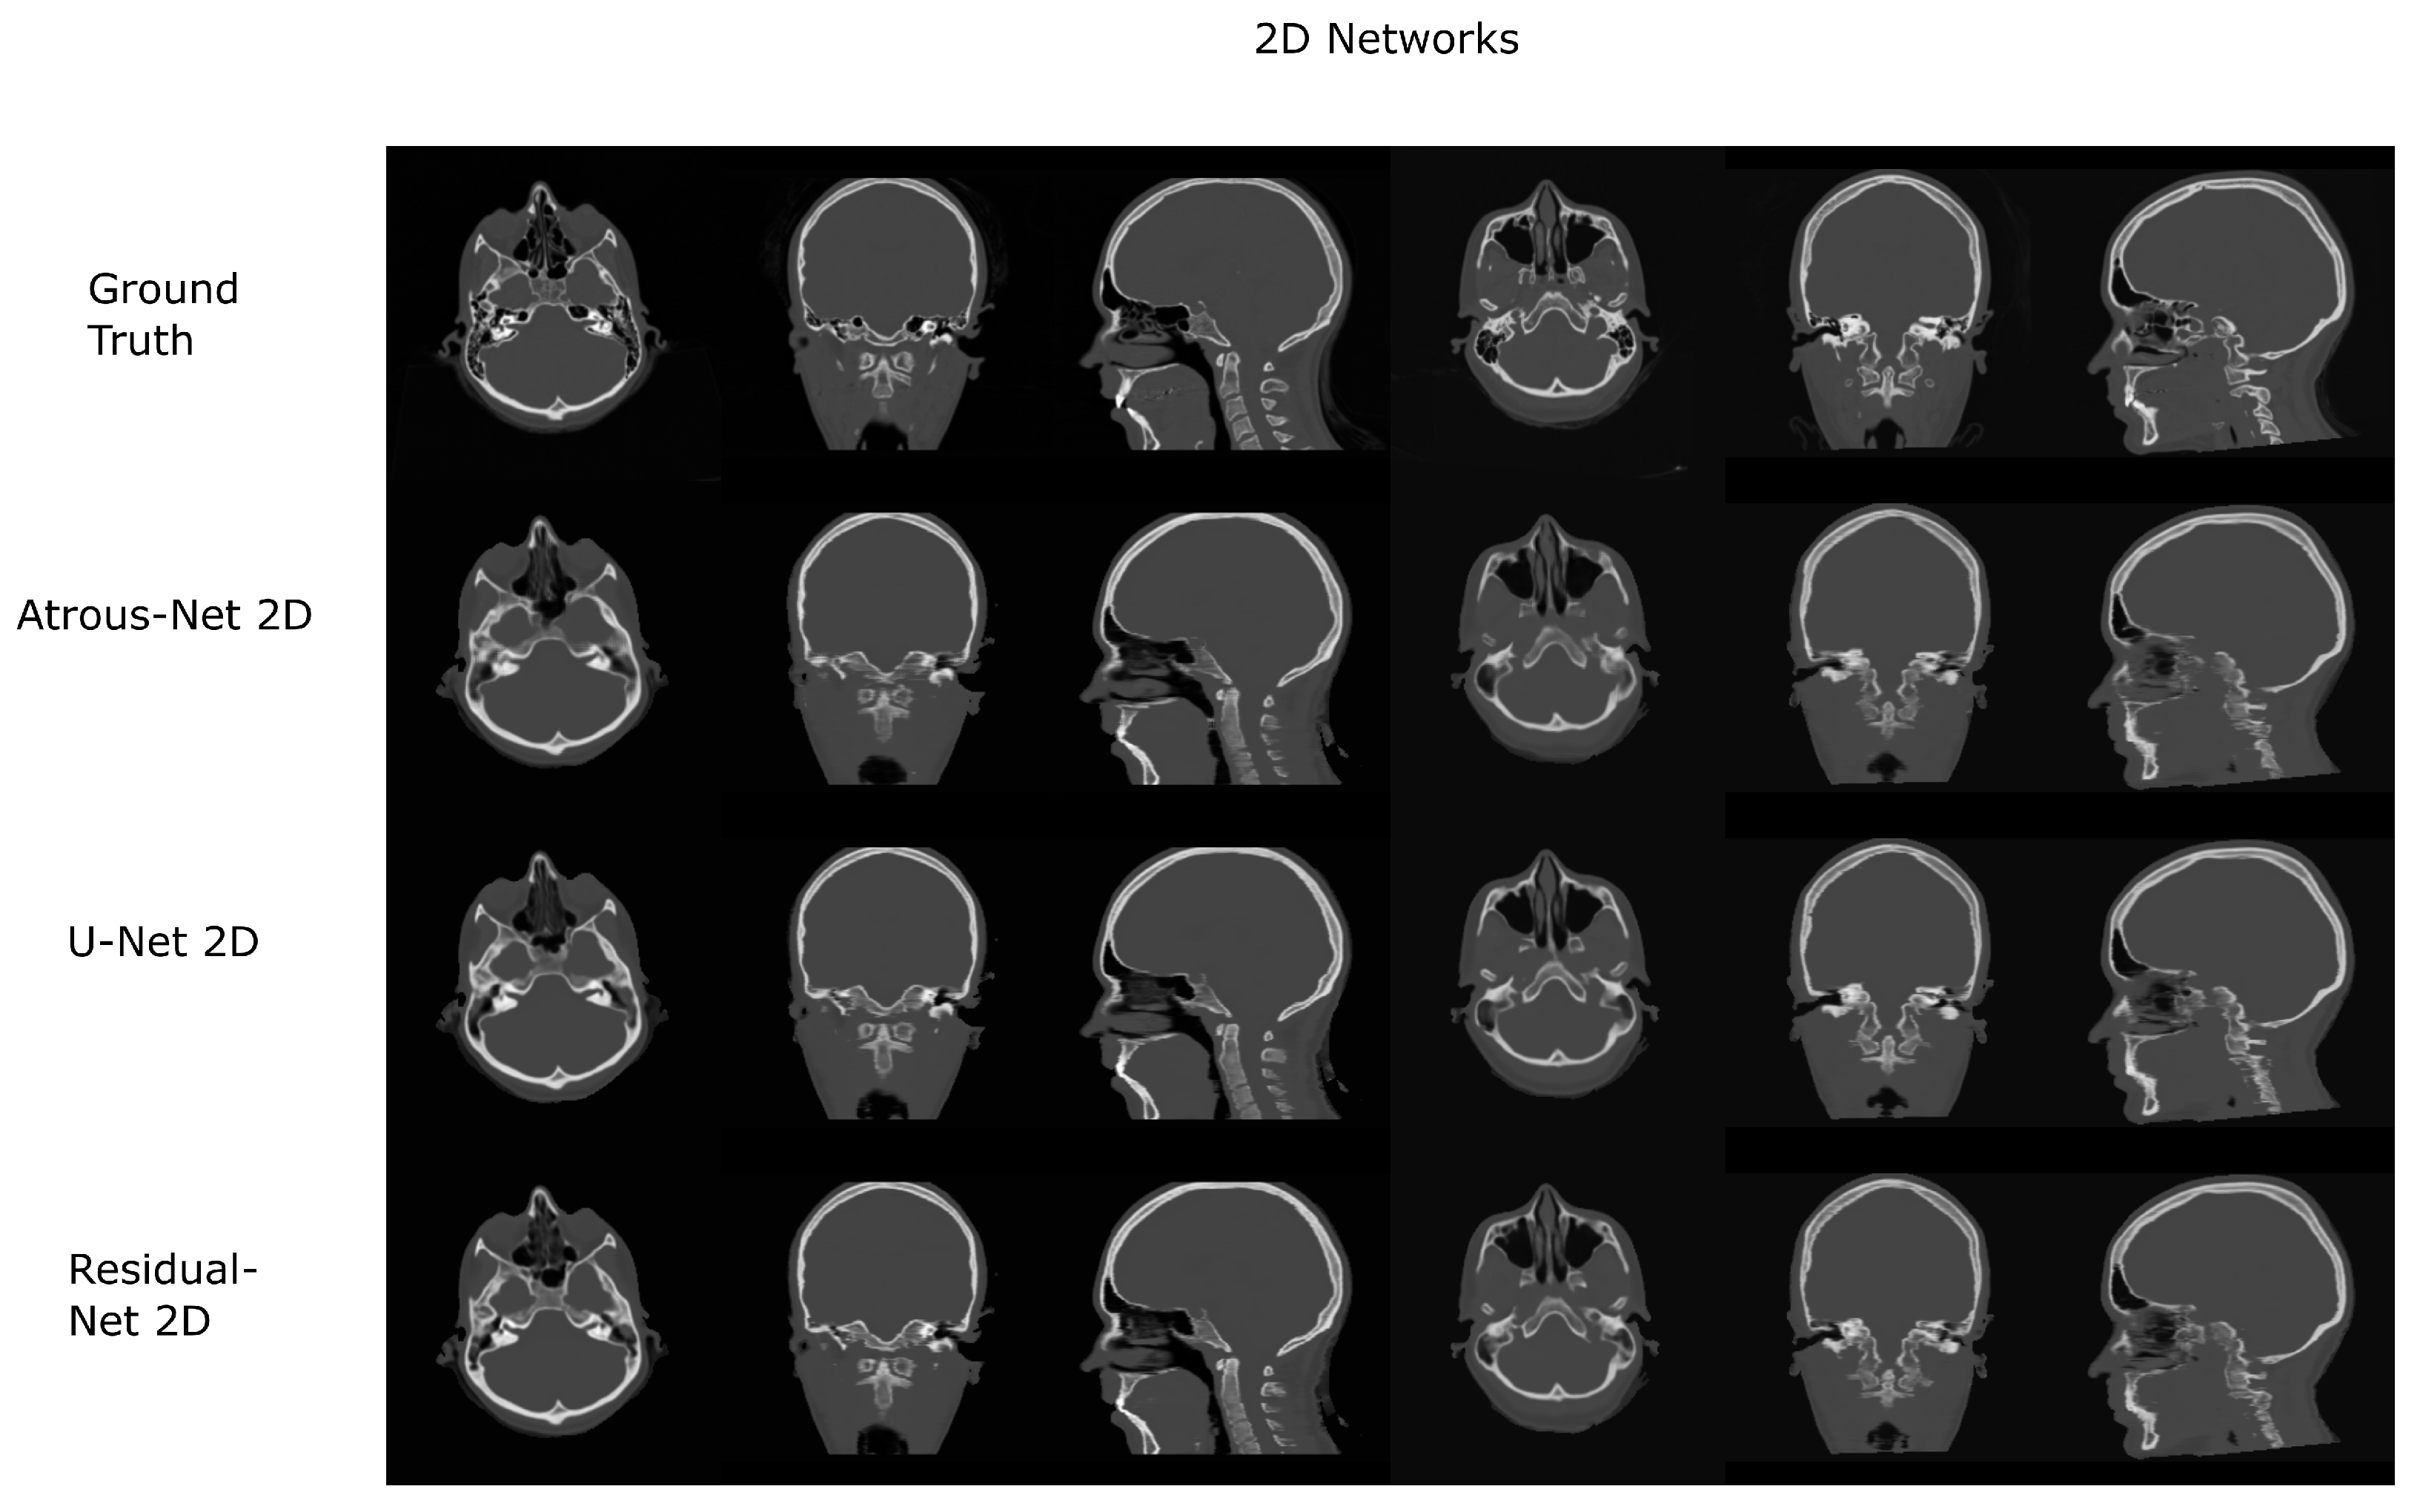

Figure 8. Pelvis results using 2D networks.

3.2. Pelvis Dataset Results

The results for all tissues using the pelvis dataset are depicted in Table 16, Table 17 and Table 18; the results using only the bone voxels are detailed in Table 19, Table 20 and Table 21; the results using only the fat voxels are detailed in Table 22, Table 23 and Table 24; and the results using only the soft-tissue voxels are detailed in Table 25, Table 26 and Table 27. In the pelvis dataset all networks performed very similar when all tissues were considered. However, 3D networks obtained slightly worse results when assessing bone alone and very similar results for all tissues. The best network in the bone dataset was the 2D Residual network that obtained a MAE of 201.56 HU, a PSNR of 23.20 and a Pearson Coefficient of 0.476 in the bone. Additionally, the error in bone with all networks increased when the 3D scheme was used. The ANOVA test for the 2D results reported a statistically significant effect of the networks in all tissues and bone MAE (all tissues: F 2 , 56 = 6.7 , p < 0.005 ; bone: F 2 , 56 = 8.5 , p < 0.001 ) and PSNR (all tissues: F 2 , 56 = 8.5 , p < 0.001 , bone: F 2 , 56 = 5.3 , p < 0.01 ). According to 3D results, the ANOVA test did not expose statistically significant differences when using different architectures on all tissue MAE (all tissues: F 2 , 56 = 2.3 , p = 0.10 ; bone: F 2 , 56 = 6.2 , p < 0.005 ) and PSNR (all tissues: F 2 , 56 = 1.4 , p = 0.25 ; bone: F 2 , 56 = 4.3 , p < 0.05 ). Post hoc Student’s t-test is depicted in Table 28 and Table 29. It reveals that the Residual-net and Atrous-net did not provide statistically significant differences. Visual result examples of pelvis pseudo-CTs are depicted in Figure 8 and Figure 9. Table 30 shows the time needed to synthesize a whole pelvis volume using the different architectures.